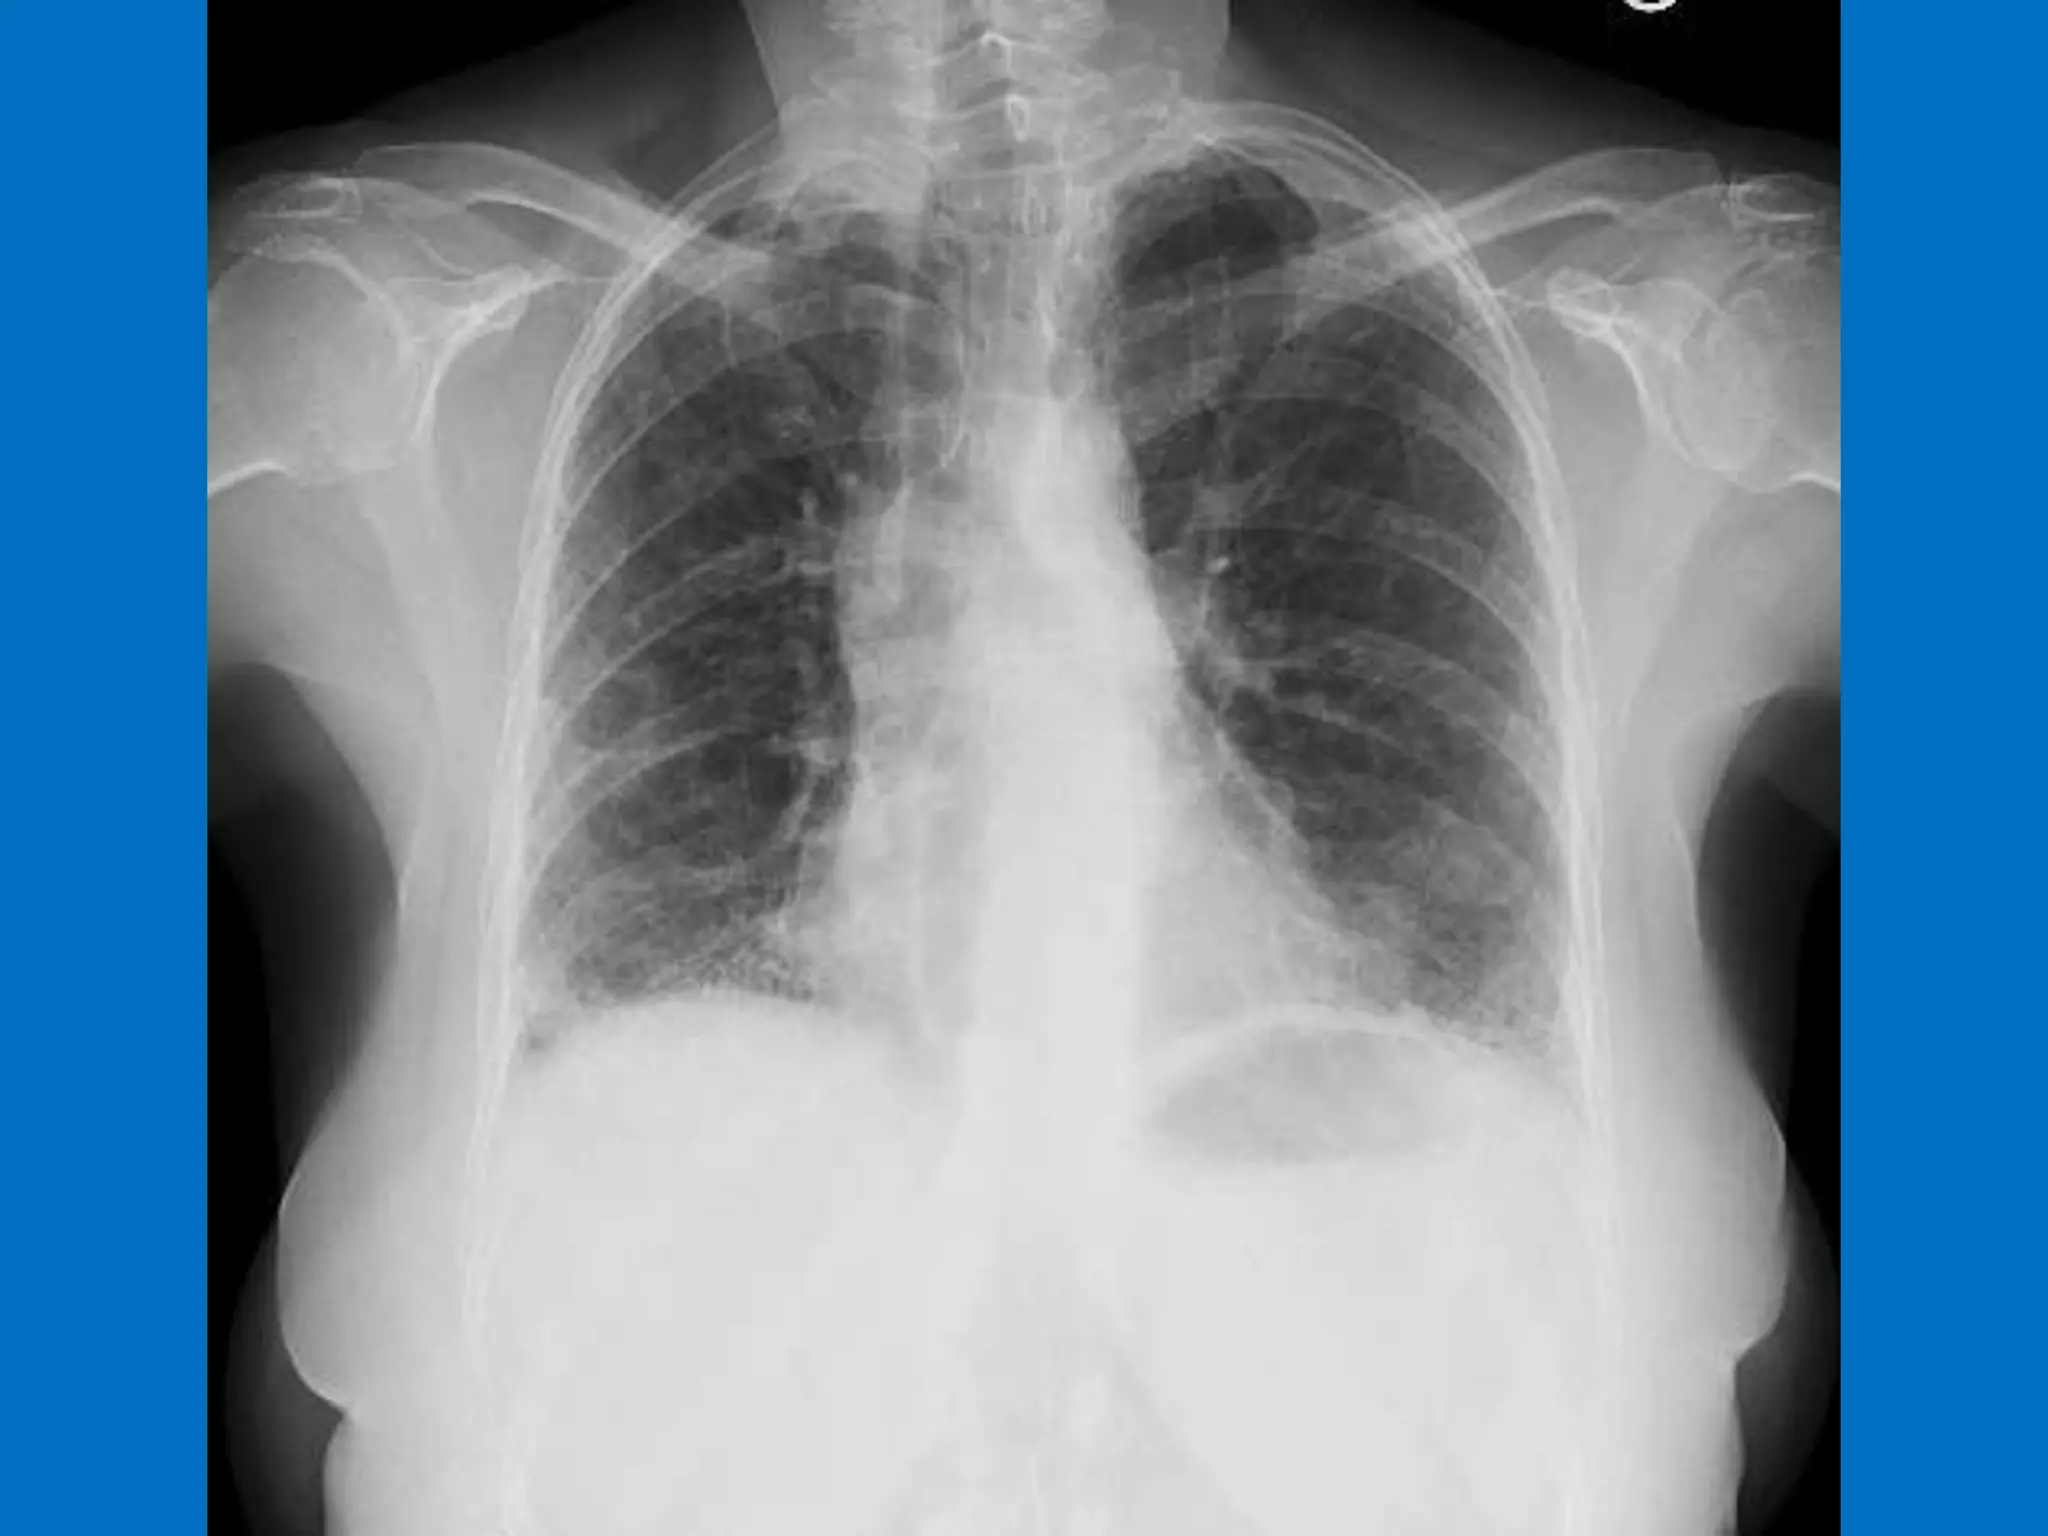

Scleroderma lung disease encompasses various respiratory complications, including interstitial fibrosis and alveolar ductitis, which are prevalent in patients. Recent research has identified differential gene expression in lung fibroblasts and new treatment options like antifibrotic and anti-inflammatory drugs. Despite the challenging prognosis, ongoing studies are promising in elucidating the disease mechanisms and potential therapeutic targets.